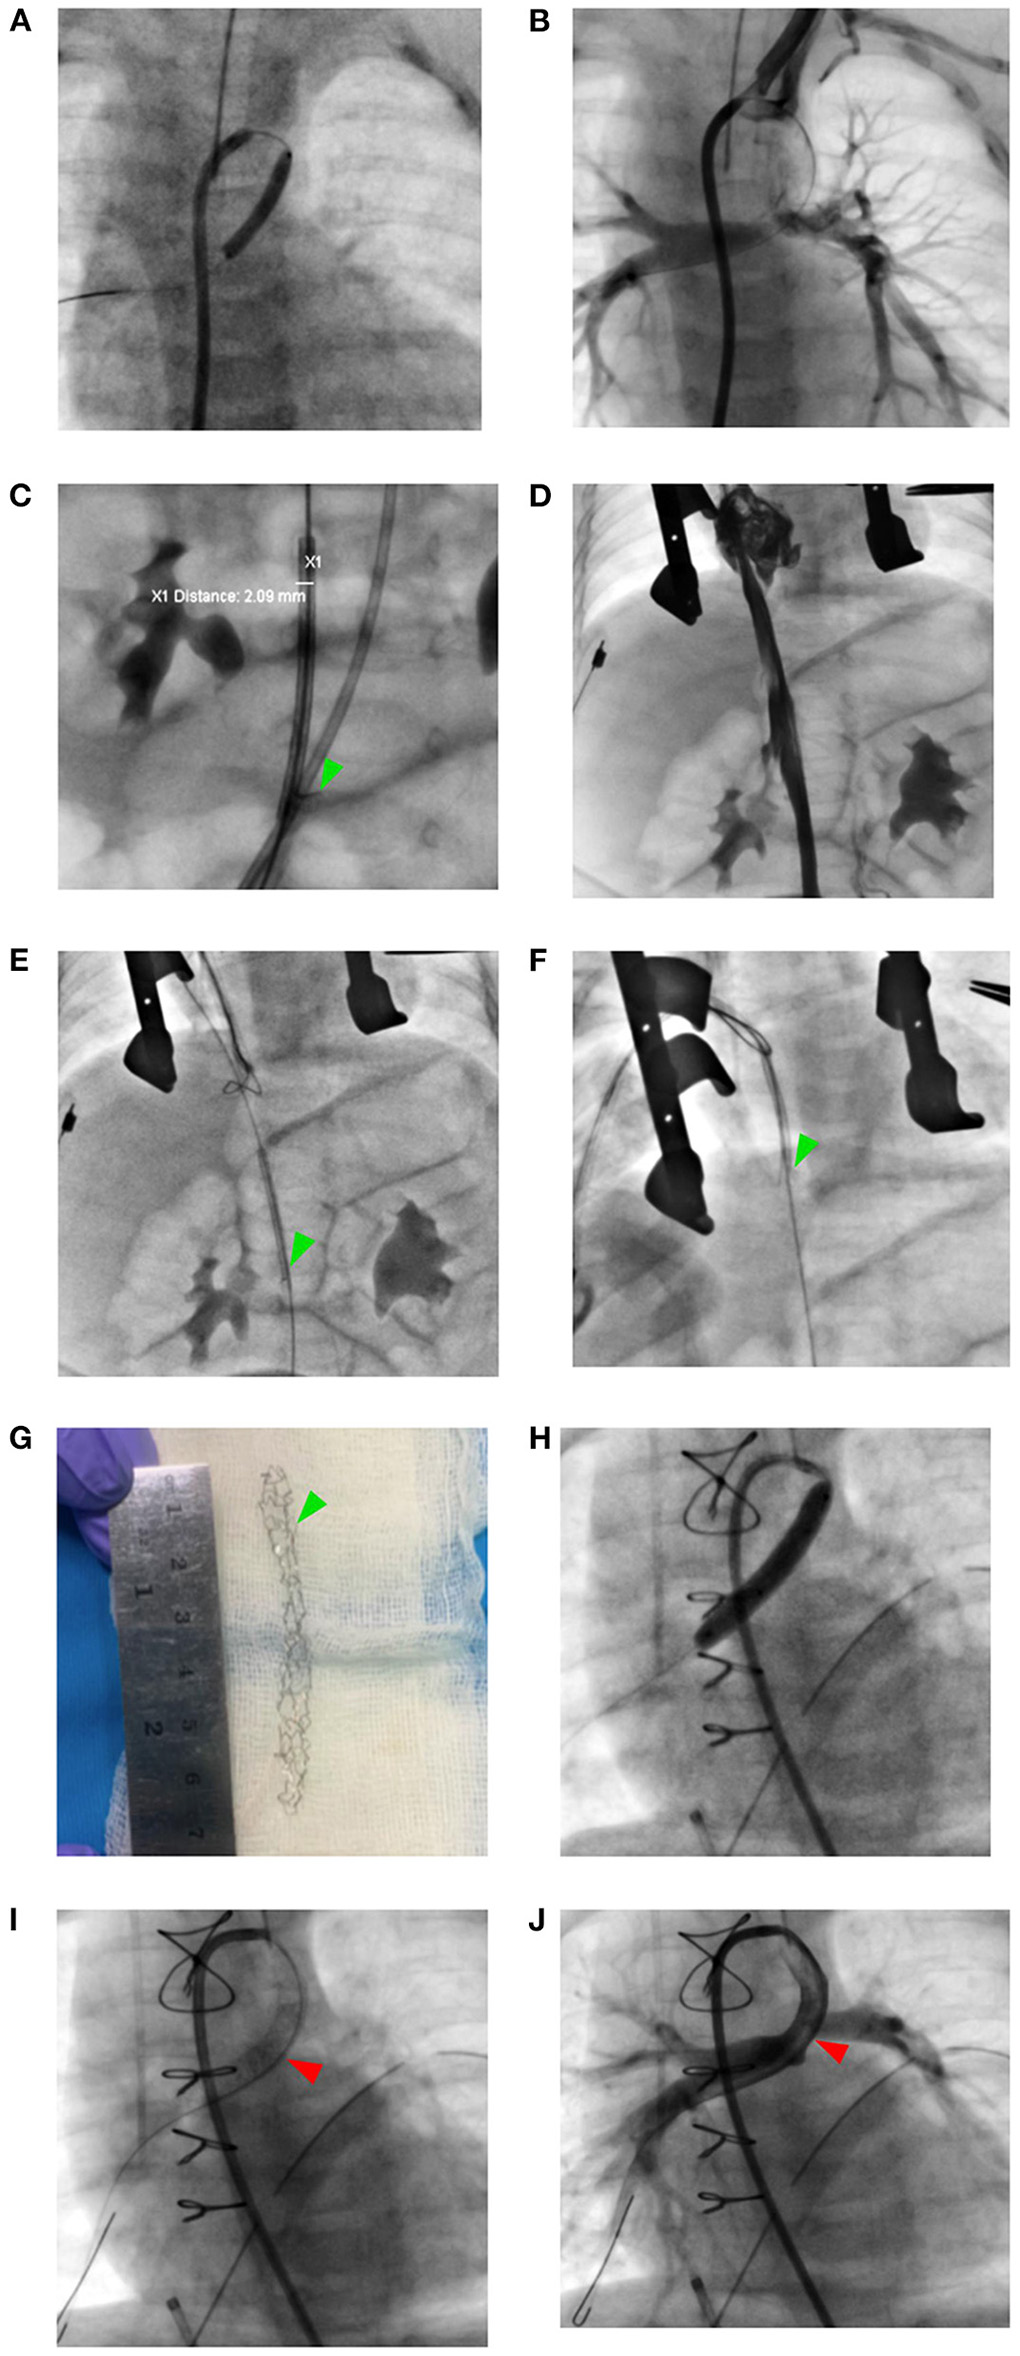

A three-month-old boy (5.4 Kg) with severe cyanosis and diagnosed with type-II pulmonary atresia, subaortic 6.5 mm-large ventricular septal defect (VSD), and patent ductus arteriosus (PDA) with the saturation of only 40% was sent for femoral transvenous ductal stenting (DS). The case was discussed in a multidisciplinary meeting and DS was found more reasonable than surgical valvulotomy (Figure 1). From the right femoral vein, a 4-Fr 3.5 Judkins Right catheter was cannulated up to the PDA across the VSD. The PDA was pre-dilated with a 3.0 x 20 mm coronary balloon that was inflated to 6 atm (Figure 2A). A 0.035″ soft exchange wire was then positioned in the right pulmonary artery and a (6.0 x 38 mm) Dynamic vascular stent was delivered into position using the naked technique. It was technically impossible to push the stent inside the PDA because of the complex angulation (Figure 2B). The stent got stuck in the IVC upon retrieval (Figure 2C). We tried to push and pull the stent to verify that the stent is still on its wire track. Caval angiography was done to verify that the IVC was not damaged (Figure 2D). An urgent multidisciplinary decision was taken to remove the stent in the cath lab using a 10-Fr RAA hybrid access without cardiopulmonary bypass (CPB) support. The recapture of the stent was uneventfully performed using a 20 mm gooseneck snare (Figures 2E–G) and DS was successfully performed from the femoral artery with a (4.0 x 30 mm) Resolute Integrity stent that was inflated at 20 atm for 6 s (Figure 2H). Control angiography showed that the stent migrated toward the distal right pulmonary artery (Figures 2H, I). We decided to position a second stent because the PDA was not entirely covered. However, due to the complex PDA anatomy, it was technically difficult to overlap the first stent. We decided to abort our procedure since the PDA did not close at 3 months of age and the oxygen saturation had already risen to 94% (see Figure 2J). There were no vascular access complications. The follow-up was clinically satisfactory and the patient underwent Rastelli surgery age at 11 months with good outcomes.

Figure 2

Stucked stent retrival strategy from the inferior vena cava and transarterial restenting the ductus arteriosus. (A) Ductal pre-dilation with an Ikazuchi coronary balloon 3.0 x 20 mm. (B) Failure to deliver the Dynamic vascular stent within the ductus arteriosus. (C) The stent strutted in the inferior vena cava (green arrowhead). (D) Caval angiography showing no vascular trauma. (E–G) Stent Evacuated through right atrial appendage hybrid access with 20 mm gooseneck snare. (H, I) Transarterial ductal restenting with Resolute Integrity 4.0 x 30 mm stent (red arrowhead). (J) Post-stenting ductal angiography.